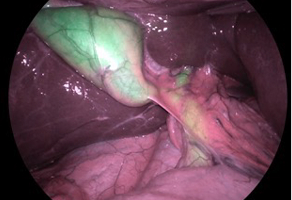

Yellow Enhancement (YE)

Yellow Enhancement (YE) is a default function of the VISERA ELITE™ III surgical imaging platform, designed to enhance the difference in visualization between material that contains yellow and material that does not. This is achieved through color conversion, where orange material appears as enhanced yellow. This visualization is related to the presence of beta-carotene in fat, which is one of the few materials in the abdominal cavity containing yellow.

In a 2025 survey, 8 out of 10 surgeons surveyed agreed that YE may assist in identifying vessels, nerves, and critical structures within adipose tissue.4